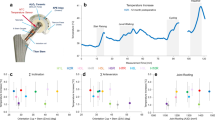

From the estimated resultant HCF, a typical curve characterized by two peaks can be observed in all performed simulations. Specifically, for the starting reference configuration a maximum resultant HCF of 2679 N (3.2 BW) was computed at the first peak in the gait cycle (Fig. 4a), which remained almost unvaried (max variation < 29 N) after changes in prosthesis parameters. Conversely, the greatest resultant HCF alteration was observed at the characteristic second peak of the gait cycle, corresponding to the terminal stance phase. The observed force variation rises from 2604 N up to 2697 N (+3.5 %) in case of shorter implant offsets, while it decreases to 2516 N (−3.4 %) for longer offsets. Looking at the force components (Fig. 4b), it can be derived that the HCF alteration belongs mainly to the y-component of the force (directed along the femoral neck axis), which shows the highest force values followed by the x-component. The z-component, perpendicular to the coronal plane, is not importantly affected by the prosthesis variations.

With reference to the contact location on the femoral head during the stance phase of the gait cycle (Fig. 4c), a negligible alteration in the contact point trajectory was observed among the different configurations (Supplementary Table S2). In general, the contact point moves anteriorly along an arc path located apically on the femoral head roughly surrounding the y-axis of the local reference system.

In Fig. 5, the results obtained at the end of the application of MB-derived loads on the head surface are presented. The reference configuration exhibited a maximum CSLIP of 1.91 μm in the distal-medial area of the trunnion at 14% (t2) of the gait cycle (i.e., the start of the mid-stance phase). Negligible changes were observed due to neck length variation (Fig. 5a), for which the maximum difference with the reference curve was found at 52% of the gait cycle (t4) for the short neck and corresponded to around 3% of the reference value at the same time step. In contrast, the variation in head size (Fig. 5b) led to considerable changes in micromotions. While a smaller head size (S-size) resulted in a reduction of the maximum CSLIP to 1.32 μm, a greater head size (L-size) led to a maximum CSLIP of 2.81 μm. In addition, the combined variation of both parameters to maintain the same implant offset (Fig. 5c) resulted in comparable outcomes to those with the only variation in head size. In this scenario, the maximum CSLIP was consistently in the same location with a value of 2.79 μm. Furthermore, micromotions were determined for the reference configuration by applying the MB-derived forces and torques at the center of the head. Under such boundary conditions, the CSLIP peak previously computed at t2 decreases by approximately 20%, underestimating the micromotions at the conical junction. A detailed comparison of outcomes deriving from the two alternative boundary conditions is provided in the supplementary material (Supplementary Fig. S5).

Finally, Fig. 6 depicts the vector plot of the CSLIP for the configuration with the L-size head at t2. From the calculation of the single components of the CSLIP in cylindrical coordinates, it is possible to observe that the longitudinal component (Fig. 6a) is predominant in this time step (2.78 μm) and it is located in the distal-medial area of the trunnion. The maximum value in the tangential component (Fig. 6b) was equal to 0.80 μm, localized in the medial-posterior distal area. In the same time step, the maximum radial compression of the trunnion is also localized (Fig. 6c) near the peak of the longitudinal component, corresponding to 0.12 μm. The maximum values of the three components are reported in the graph in Fig. 6d.